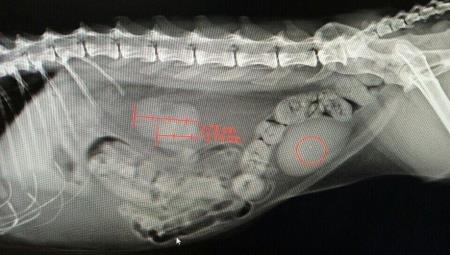

贫血是指单位容积的血液中血细胞数、血红蛋白含量及红细胞压积容量(比容)容)低于正常值以下。

再生障碍性贫血是一组由多种病因所致的骨髓造血功能衰竭性综合征,以骨髓造血细胞增生减低和外周血全血细胞减少为特征。

再生障碍性贫血临床症状的发展比较缓慢,除有上面提到的三种的贫血症状外,主要表现在狗狗的血象变化上,红细胞及白、红蛋白含量低,血液中网状红细胞消失。

【症状】再生障碍性贫血临床症状的发展比较缓慢,除有以上三种的贫血症状外,主要表现在血象变化,红细胞及白、红蛋白含量低,血液中网状红细胞消失。